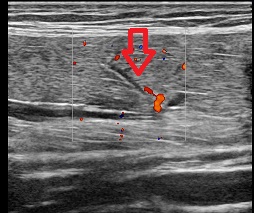

1.太ももの肉離れ